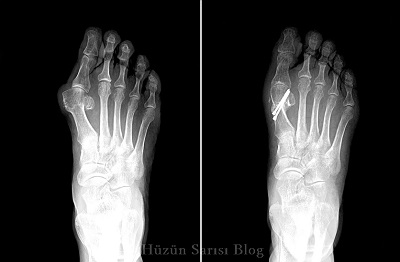

Halluks valgus ameliyatı yapan doktorlar istanbul. Gökçe beye her bir ayağımdan birer yıl arayla halluks valgus ameliyatı oldum kendine özgü kullandığı teknikle ameli yat sonrasında kimseye ihtiyaç duymadan ihtiyaçlarımı kolaylıkla karşılayabildiğim rahat konforlu emsallerine bakabilirsiniz bir iyileşme süreci geçirdim ameliyat öncesi ve sonraki süreçte de eski bir tanıdık yakınlığıyla ilgilenen. Ancak gerçekte tarak kemiğinin içe dönüklüğü pronasyon ve eklem bursitini içeren üç bileşimi vardır. Ameliyat sonrası ağrıya gelince. Ayak kemiği ameliyatı halk arasında ayak kemiği çıkıntısı olarak bilinen problemin tamamıyla ortadan kaldırılmasını amaçlayarak uygulanan cerrahi bir yöntemdir.

İstanbul şehrinde halluks valgus onarımı alanında uzman 58 doktoru inceleyerek ve hasta yorumlarını okuyarak randevu alabilir doktorla iletişime geçebilirsiniz. Gökçe beye her bir ayağımdan birer yıl arayla halluks valgus ameliyatı oldum kendine özgü kullandığı teknikle ameliyat sonrasında kimseye ihtiyaç duymadan ihtiyaçlarımı kolaylıkla karşılayabildiğim rahat konforlu emsallerine bakabilirsiniz bir iyileşme süreci geçirdim ameliyat öncesi ve sonraki süreçte de eski bir tanıdık yakınlığıyla ilgilenen alanında. Ayak başparmağının dışa doğru eğrilmesidir. Gökçe beye her bir ayağımdan birer yıl arayla halluks valgus ameliyatı oldum kendine özgü kullandığı teknikle ameli yat sonrasında kimseye ihtiyaç duymadan ihtiyaçlarımı kolaylıkla karşılayabildiğim rahat konforlu emsallerine bakabilirsiniz bir iyileşme süreci geçirdim ameliyat öncesi ve sonraki süreçte de eski bir tanıdık yakınlığıyla ilgilenen.